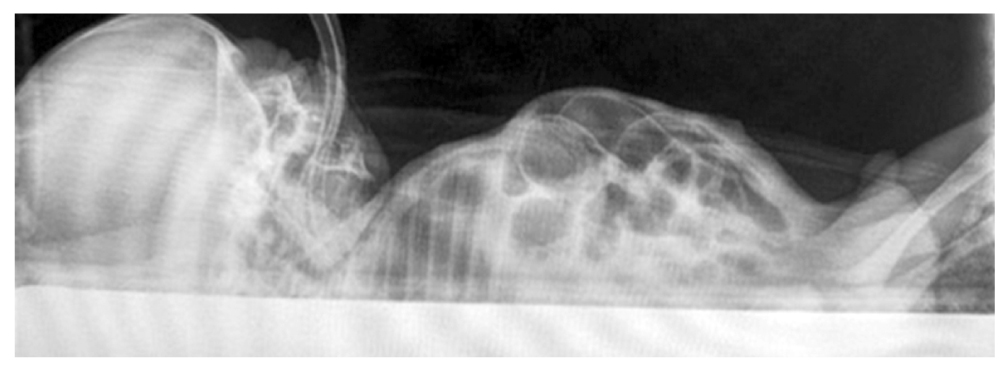

Обзорная рентгенограмма брюшной полости: в латеропозиции свободный газ обнаруживается под передней брюшной стенкой (рис. 1).

Рис. 1. Рентгенограмма органов брюшной полости в латеропозиции. Воздух определяется под передней брюшной стенкой.

Fig. 1. Radiograph of abdominal organs in the lateral position. Air is detected under the anterior abdominal wall.